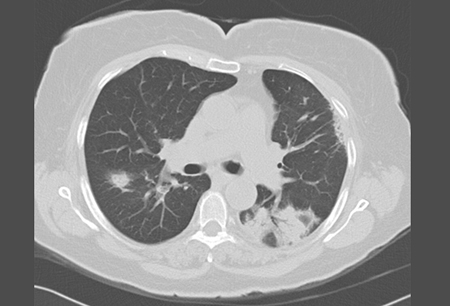

Tomografia computadorizada de alta resolução (TCAR) do tórax mostrando opacidades bilaterais em vidro fosco e um infiltrado com base triangular posterior com broncograma aéreo

Do acervo de Gary R. Epler, MD